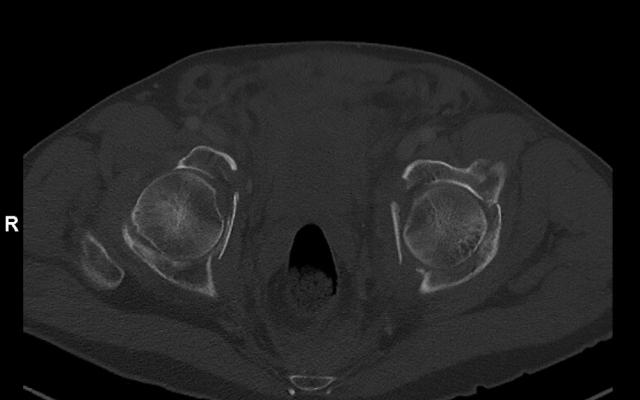

Een 38-jarige zwangere vrouw werd bij een amenorroeduur van 31/5 weken op de Spoedeisende Hulp gezien vanwege een gegeneraliseerd tonisch-clonisch insult. De waarschijnlijkheidsdiagnose was een eclamptisch insult vanwege hypertensie bij opname. Ondanks behandeling met magnesiumsulfaat had zij recidiverende insulten. Daarom werd beeldvormend onderzoek verricht. Er bleek sprake van een hooggradig glioom. De patiënte is bij 37 weken zwangerschap bevallen van een gezonde dochter en werd daarna palliatief behandeld met chemotherapie.